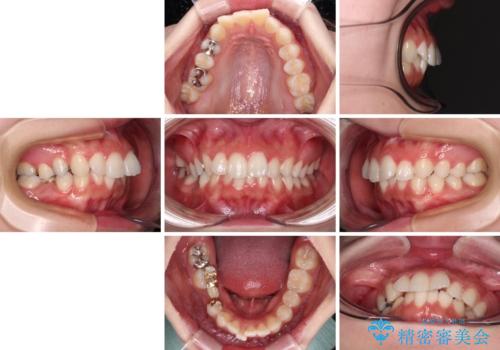

欠損した歯と前に飛び出した前歯 インプラント治療を併用したワイヤー矯正治療

- 上の前歯が下唇に当たる感覚と奥歯の欠損を気にして来院された患者様です。

上顎前歯の突出感は、上顎全体が前方に位置していることが原因であったため、補助装置により上顎全体を後方に移動させることとしました。

後方移動と同時上下歯列をワイヤー装置にて整え、奥歯の欠損部には矯正治療の途中でインプランを埋入していくこととしました。